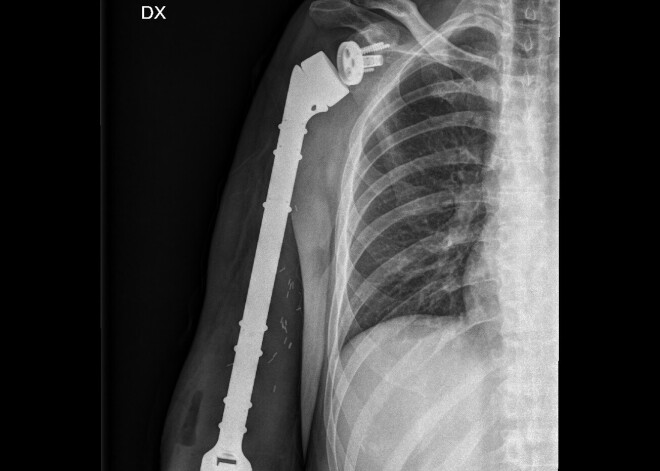

Izvērtējot radioloģiskos izmeklējumus, bija pārliecība, ka var veikt ekstremitāti un tās funkcionalitāti saglabājošu operāciju, ievērojot onkoloģiskās radikalitātes principus- izņemt visu audzēju vienā blokā, to neatverot, pie tam saglabājot visus asinsvadus un nervus, kā arī muskuļus. To izdarot, ir nepieciešams aizvietot ne tikai izņemto kaulu, bet arī pleca un elkoņa locītavu ar endoprotēzi- lai roka kustētos.

8 stundas garā operācijā, kurā piedalījās ārsts traumatologs, ortopēds Lauris Repša, traumatoloģijas, ortopēdijas rezidents Andris Levis, ārsts anesteziologs Jeļena Solovjova, operāciju māsas Ilona Jevsejeva un Aija Avotiņa, anestezioloģijas māsa Anda Bukša, tika veikta visa labā augšdelma kaula un audzēja izņemšana, un rekonstrukcija ar endoprotēzi.

Pēc operācijas pacientam uzsākta intensīva fizioterapija fizotearpeites Ilzes Vindeles uzraudzībā. Audzējs ir izņemts pilnībā, kas pacientam dod labas nākotnes prognozes, un ir izdevies saglabāt pilnībā funkcionālu labā elkoņa un plaukstas locītavu. Pacients arī turpmāk būs spējīgs veikt ikdienas aktivitātes, atklāj slimnīcā.